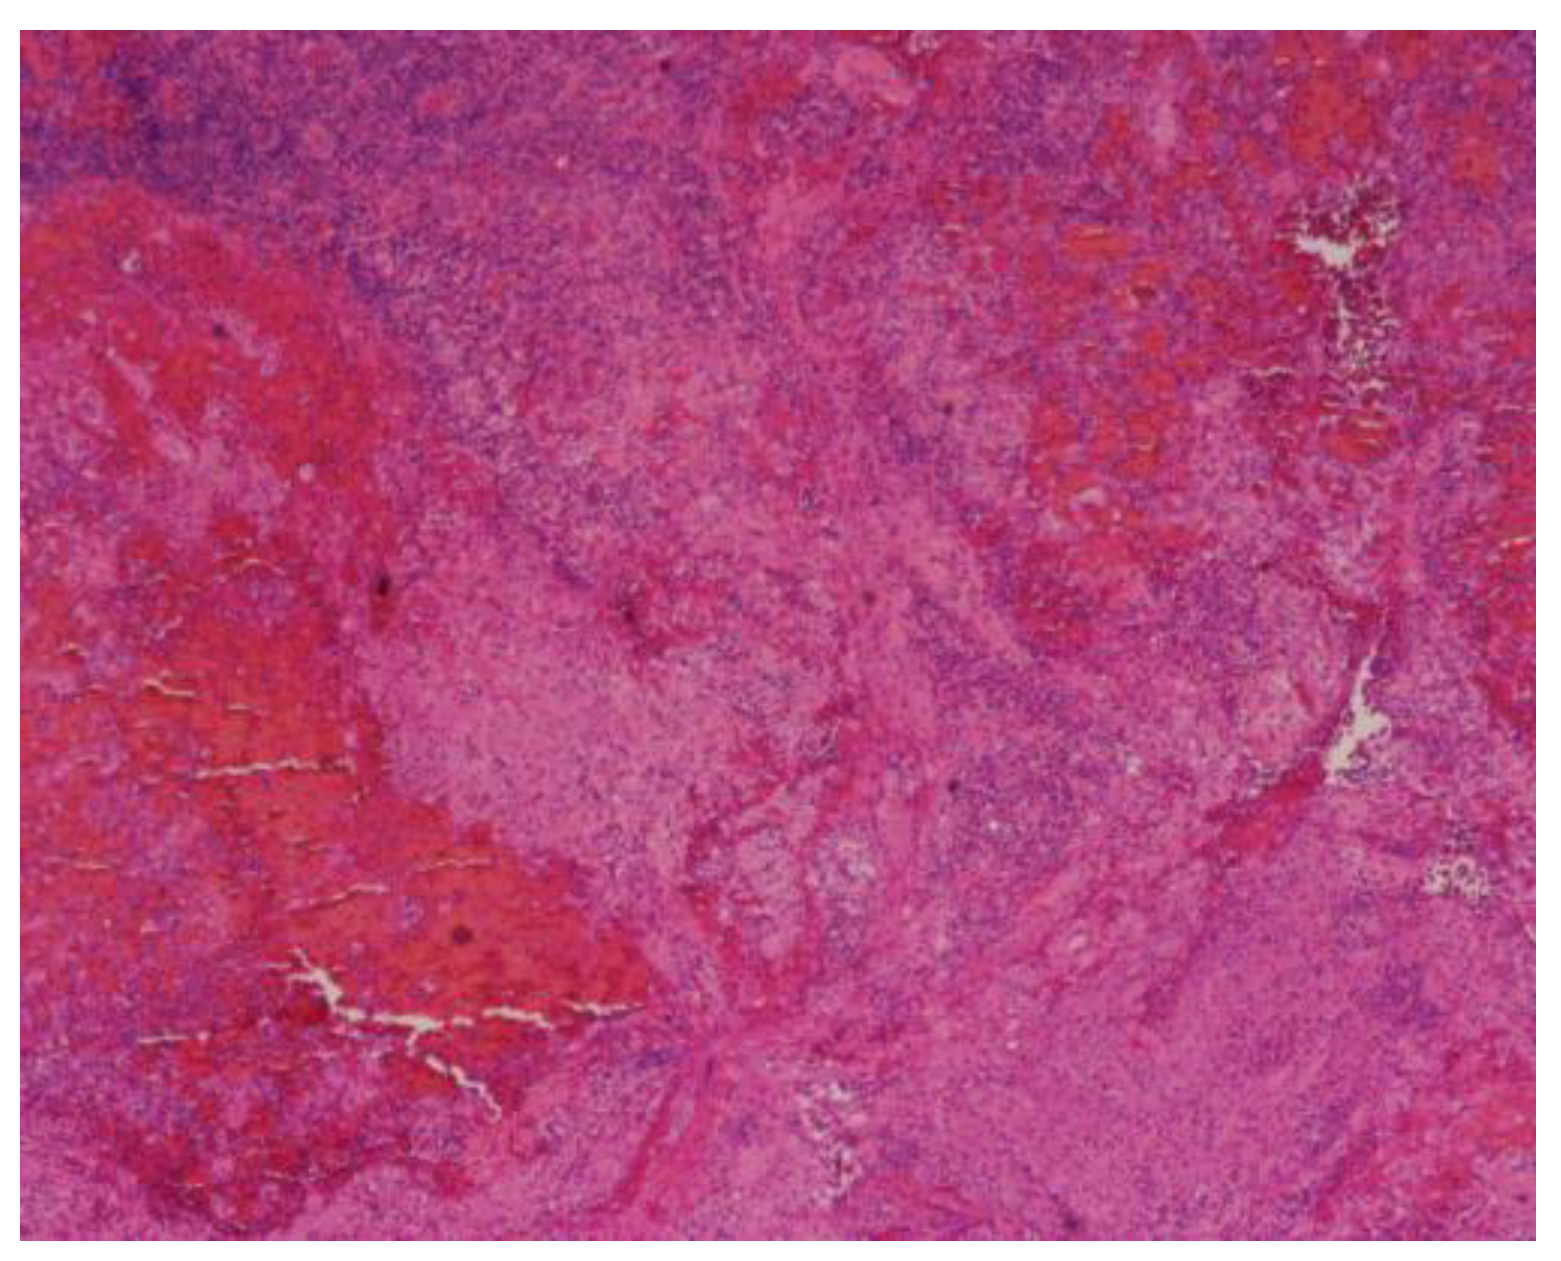

A 63-year-old man, previously healthy and living in a rural area, presented with a 5-month history of hemoptysis, pleuritic pain, weight loss of 14 kilograms, and night sweats. One month before admission he had been diagnosed initially with community-acquired pneumonia at his local hospital however, no information about the treatment was available. At admission, the patient was in poor general condition with tachycardia, fever, and tachypnea. Physical examination revealed no abnormalities in the cardiopulmonary and skin exam. The initial investigation showed a high C-reactive protein (10.74 mg/dL; reference range: 0-0.3 mg/dL), leukocytosis (21,800/mm3; reference range: 5,000-10,000/mm3), neutrophilia (19,900/mm3; reference range: 4,000-7,000/mm3), and a chest X-ray with parenchymal consolidation in the right upper lobe and poorly defined opacities in the middle lobe (Figure 1). A contrasted computed tomography scan of the chest showed extensive pulmonary parenchymal involvement in the right upper lobe and middle lobe and an anterior mediastinal mass with central necrosis and enhancement of its contours (Figure 2).

Figure 3. Mediastinal mass biopsy. Hematoxylin-eosin staining at 4x shows histiocytes aggregates and hemorrhage.

Figure 1. Chest radiograph. A posteroanterior view revealed consolidation in the right superior lobe and poorly defined opacities in the middle lobe.